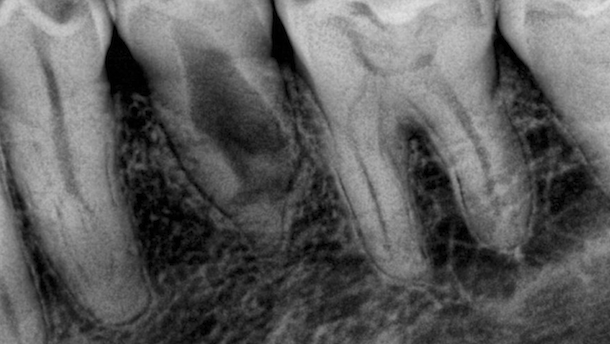

Paciente de 46 años que se presenta en la consulta por un cambio de color en la corona del diente 35 (segundo premolar inferior izquierdo). Clínicamente, las pruebas de sensibilidad al frío y al calor son negativas. Acusa percusión dolorosa. Radiográficamente (Figura 1), se observa un conducto de forma irregular compatible con reabsorción interna (Figuras 2, 3, 4). Diagnóstico: necrosis pulpar posterior a reabsorción interna.

Se procede a realizar una obturación con inyección de gutapercha termoplastificada (termoreblandecida) mediante la pistola de Back Fill (Meta Biomed) (Figura 5) previo a la utilización de cemento sellador resinoso AdSeal (Meta Biomed) (Figura 6), el cual fue llevado con la ayuda de lentulos (Dentsply Maillefer).